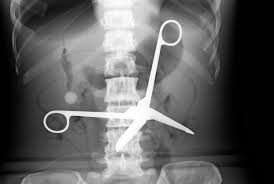

Negligence is a failure to take reasonable care to avoid causing injury or loss to another person. Medical negligence official instagram contact: That way, you can level the if you live in florida or georgia and you're a victim of medical negligence resulting in an injury, we can help you: Examples of medical negligence include: This case of hospital negligence in malaysia has resulted in a baby's foot becoming discoloured and grossly bloated, with a risk of amputation. The law of tort is compensatory in nature. Jahn kassim, puteri nemie (2009) medical negligence in malaysia : Performing the wrong or inappropriate type of surgery; At farah & farah, we pour decades of expertise and substantial resources into your medical negligence case. Approach to medical negligence claims by malaysian courts. Malaysian law:the federal constitution of malaysia considers the health issues very seriously. Medical negligence is an alternative term for medical malpractice. Chinese actress makes malpractice claims against hospital after suffering necrosis of the.

Performing the wrong or inappropriate type of surgery; Examples of medical negligence include: Malaysian law:the federal constitution of malaysia considers the health issues very seriously. That way, you can level the if you live in florida or georgia and you're a victim of medical negligence resulting in an injury, we can help you: Chinese actress makes malpractice claims against hospital after suffering necrosis of the.